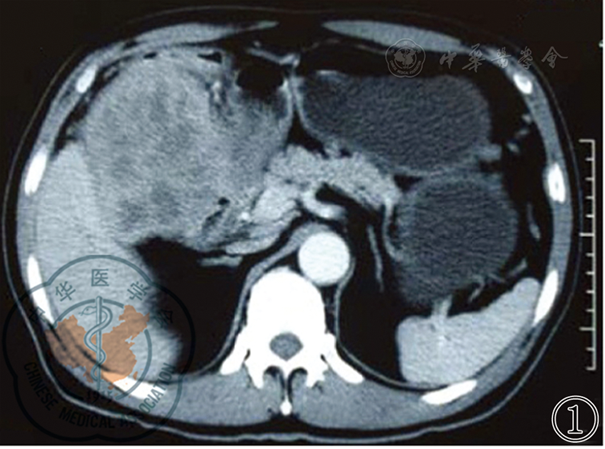

图1 术前CT检查示结肠肝曲巨大肿瘤

图2 术前CT检查示结肠肝曲肿瘤侵犯胰头十二指肠